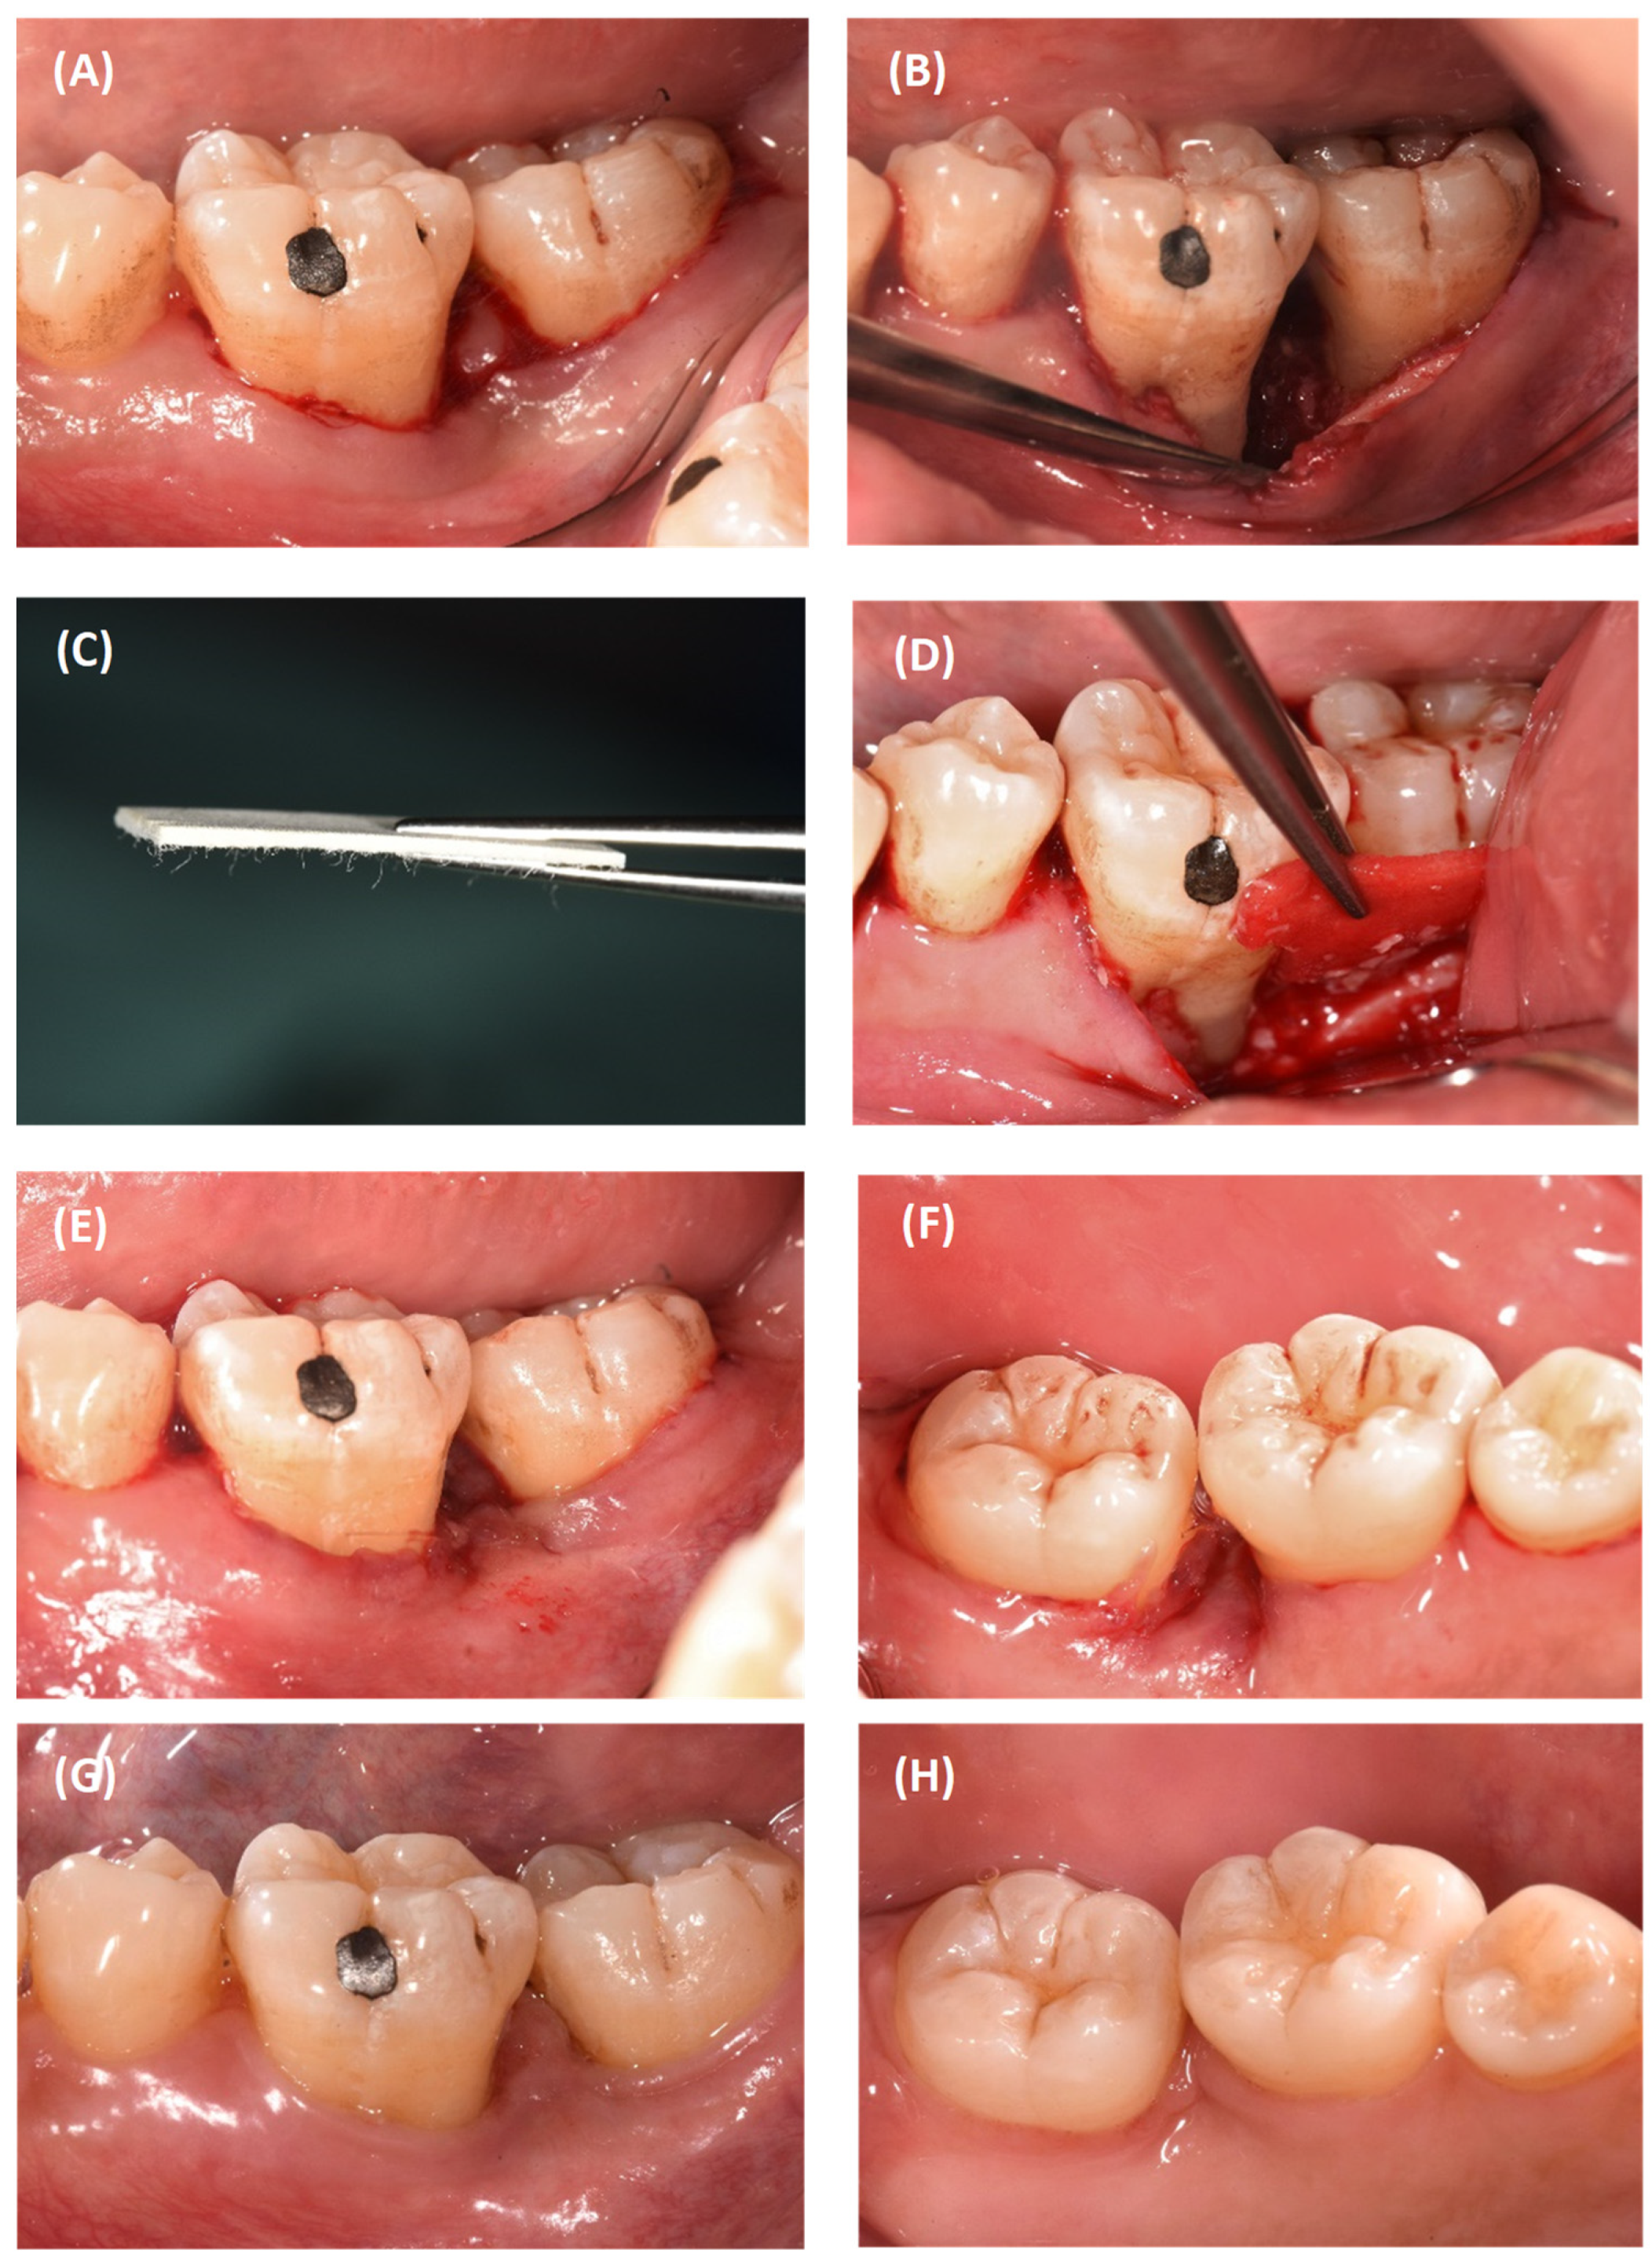

2.2. Case 2